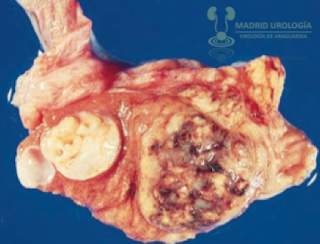

Carcinoma de Células

Embrionarias 20 %

Existen dos variedades de Carcinoma de Células Embrionarias: el tipo Adulto (Relacionado a NISCG) y el tipo Infantil o

Tumor de Saco Vitelino (No relacionado a NISCG)

(también llamado Tumor del Sinus

Endodermal). La estructura histológica de la variante adulta demuestra un

marcado pleomorfismo y ribetes de células indistintas. Las figuras mitóticas y

células gigantes son comunes. Las células pueden estar dispuestas en láminas,

cordones, glándulas, o estructuras papilares. Pueden observarse extensas zonas

de hemorragia y necrosis.

|

| Carcinoma embrionario con nodulo grande mostrando zonas de hemorragia y necrosis. Para MU con fines docentes. |